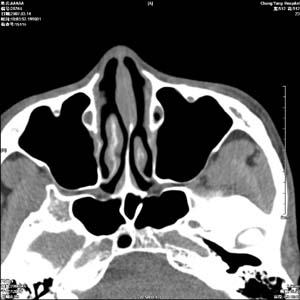

海绵状血管瘤(cavernoushemangioma)因肿瘤内为海绵样血管窦腔而得名。是成年人最常见的原发于眶内的肿瘤,占眶内肿瘤10%~23%女性较男性多见。本病为先天性错构瘤,肿瘤由大小不等的血窦及纤维间隔构成,有完整包膜。因肿瘤生长缓慢,往往在青春期后因出现眼球突出而被发现鶒曾认为海绵状血管瘤是由毛细血管瘤腔内压力增高、管腔扩张而形成的,但临床和病理均不能证实二者有因果关系。由于血管壁中查出平滑肌细胞,按血管的发育过程,属于毛细血管以后更成熟血管发生的肿瘤。